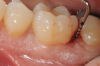

Fig 2. Tooth No. 19 at presentation, occlusal view. Note the thickness of the soft tissue and width of keratinized tissue.

Figure 2

Tooth No. 19 presented with no mobility and tested vital endodontically. Soft-tissue anatomy was intact, with a keratinized tissue width of >2 mm. The operator was experienced, with no environmental stress and used checklists. Thus, based on the presurgical risk assessment, the patient presented a low-medium risk for periodontal regenerative therapy (Table 2).